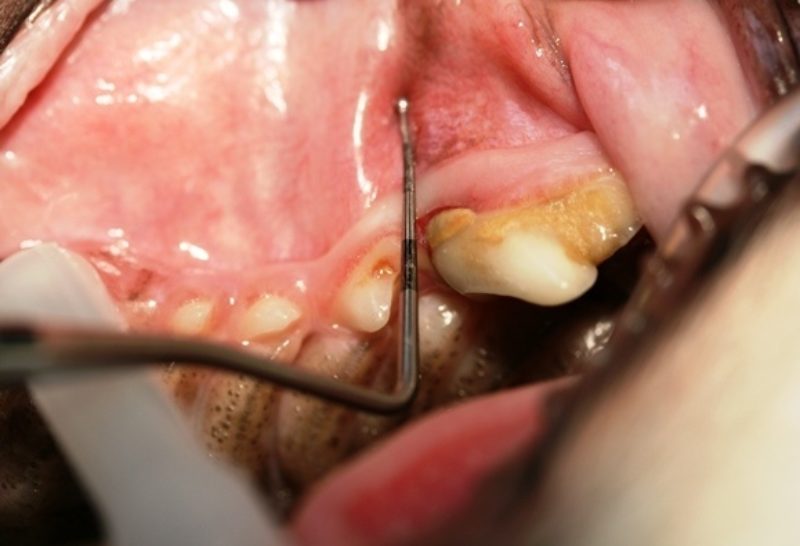

Der Chihuahua-Rüde ist sozusagen unser Zahnvorzeigepatient, und wir freuen uns jedes Jahr über seine topgepflegten Zähne, doch leider kam es anders als erwartet. Im Rahmen der gründlichen Untersuchung, die zu jeder Impfung dazugehören sollte, durfte uns Pico seine Zähne zeigen. Schnell fielen Rötung, Schwellung und Rückbildung des Zahnfleisches  im Bereich der vorderen Wurzel des Reißzahnes im linken Oberkiefer auf (Bild 1). Außerdem wies dieser Zahn im Vergleich zur Gegenseite eine deutliche Zahnsteinbildung auf. Die Parodontalsonde, ein spezielles Instrument mit einer Skalierung zum Ausmessen von Zahnfleischtaschen, brachte das Ausmaß des Schadens an das Licht. Die Sonde ließ sich fast einen Zentimeter tief in das Zahnfach einführen (Bild 2+3).